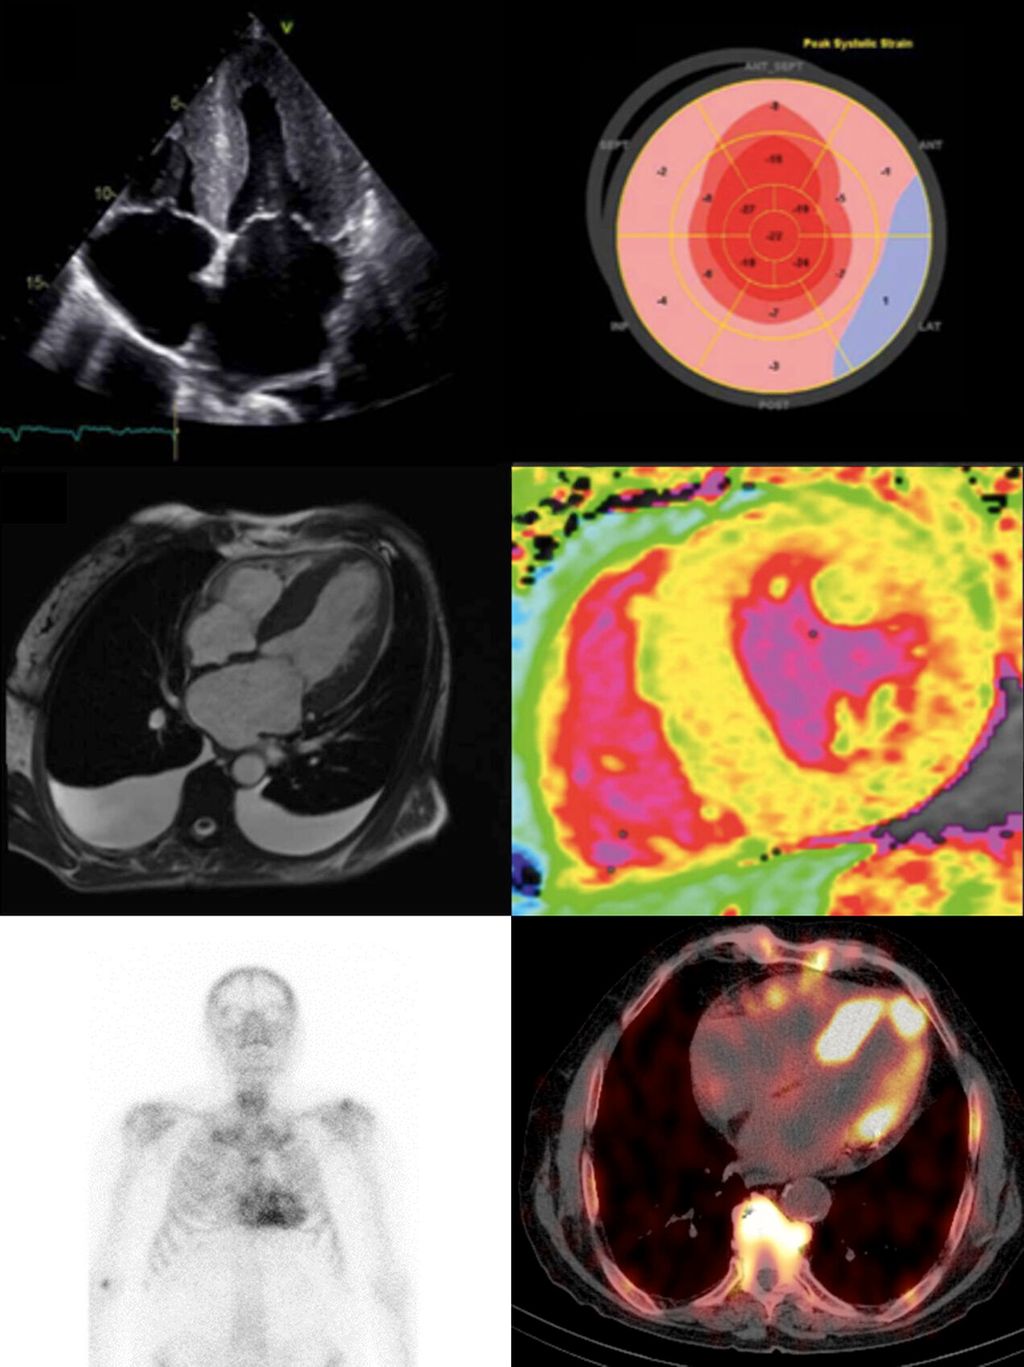

Während die ATTR-CM einst als seltene Erkrankung angesehen wurde, haben zunehmende Awareness sowie Fortschritte bei diagnostischen Methoden und Algorithmen in den letzten Jahren dazu beigetragen, dass heutzutage immer mehr Betroffene diagnostiziert werden.3 Dabei nehmen vor allem bildgebende Verfahren wie die Echokardiografie einen hohen Stellenwert ein, die anhand sogenannter „red flags“ wertvolle Hinweise auf das Vorliegen einer kardialen Amyloidose geben können. Diese umfassen eine biventrikuläre Verdickung, insbesondere im Bereich des Septums, dilatierte Vorhöfe mit hypertrophiertem interatrialem Septum, Perikard- und/oder Pleuraergüsse (Abb. 1a) sowie das charakteristische Muster einer basal reduzierten und apikal erhaltenen longitudinalen Funktion der linksventrikulären Wandabschnitte in der Strain-Analyse („apical sparing“, Abb. 1b).4 Darüber hinaus erlaubt die kardiale Magnetresonanztomografie (MRT), mittels kontrastmittelgestützter „Late-Enhancement“-Aufnahmen und T1-Mapping-Sequenzen myokardiale Amyloidablagerungen in der extrazellulären Matrix zu erfassen (Abb. 1c und 1d), wodurch eine zuverlässige differenzialdiagnostische Abgrenzung zu anderen hypertrophen Erkrankungsformen möglich ist.5

Abb. 1: Bildgebende Verfahren zur Diagnostik einer Transthyretin-Amyloid-Kardiomyopathie (ATTR-CM) (Quelle: eigene Anfertigung)

Eine diagnostische Schlüsselrolle wird jedoch nuklearmedizinischen Verfahren wie der planaren Ganzkörper-Knochenszintigrafie mit radioaktiv markierten Amyloid-affinen Tracern (wie z.B. 99mTc-DPD) zugeschrieben (Abb. 1e).6 Diese ermöglicht die Visualisierung myokardialer Amyloidablagerungen und hat sich als nichtinvasiver Goldstandard mit hoher Sensitivität und Spezifität für die Diagnose der ATTR-CM etabliert, indem die Amyloid-bedingte Tracer-Anreicherung semiquantitativ mittels des visuellen Perugini-Scores beurteilt wird.7 Hierbei gilt es jedoch anzumerken, dass die planare Bildgebung einigen Limitationen unterliegt. Dazu gehören zum einen falsch-positive Befunde aufgrund von „Radiotracer-Blutpooling“, die fälschlicherweise als Anreicherung im Myokard interpretiert werden, und zum anderen sind planare bildgebende Verfahren nicht in der Lage, den progredienten Krankheitsverlauf zu quantifizieren oder Amyloid-spezifische Therapien zu monitieren.8 Diese potenziellen Limitationen können durch quantitative Verfahren wie die SPECT/CT-Bildgebung (Single Photon Emission Computed Tomography/Computed Tomography) verringert werden (Abb. 1f).9 Anhand quantitativer Bildgebungsbiomarker, welche die Konzentrationen des radioaktiven Tracers im Gewebe widerspiegeln, kann eine umfassende Quantifizierung myokardialer Amyloidablagerungen erfolgen. Bei serieller Anwendung bietet dies zudem das Potenzial, den Krankheits- und Therapieverlauf zu überwachen.10,11